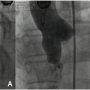

The patient was started on 150 mg aspirin/day and clopidogrel 75 mg/day. At cardiac catheterization, the aortic and pulmonary pressures were 186/58 mm Hg (mean, 100 mm Hg) and 38/12 mm Hg (mean, 20 mm Hg), respectively. The baseline left-to-right shunt was 3:1. Aortic root angiography confirmed the diagnosis (Figure 2A).

As described previously,1-3 the TCC procedure involves crossing the defect from the aortic side using a 5 Fr Judkin’s right coronary catheter and a 0.035˝ angled-tip glide wire (Terumo Inc), which is exchanged for a 300-cm long noodle wire (AGA Medical Corporation). A stable arteriovenous loop was established by snaring the noodle wire from the superior vena cava by a gooseneck snare (ev3 Endovascular Inc) and exteriorizing it from the femoral vein. Using a 6 Fr delivery sheath through the femoral vein, the 10 x 8 mm first-generation Amplatzer duct occluder (ADO; AGA Medical Corporation) was positioned across the defect. The ADO was released only after confirming on TEE as well as angiography the correct position of the ADO, not causing any significant residual shunting or any increase in aortic regurgitation. The procedure was successful (Figure 2B) and there were no conduction disturbances noticed. The patient was discharged on day 4 with an uneventful course, except for PR prolongation on predischarge ECG (PR interval of 240 ms at heart rate of 60/min) (Figure 3).